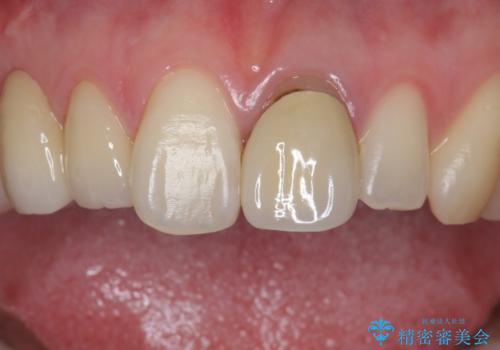

前歯を綺麗にしたい ジルコニアクラウンでの治療

- 前歯の被せ物のやり替えを希望して来院されました。

再根管治療の後、審美性の良いジルコニアクラウンをセットしていきます。

歯ぐきの状態も良く、適合の良い被せ物を入れることができました。

審美性もかなり改善され、大変喜んでいただけました。